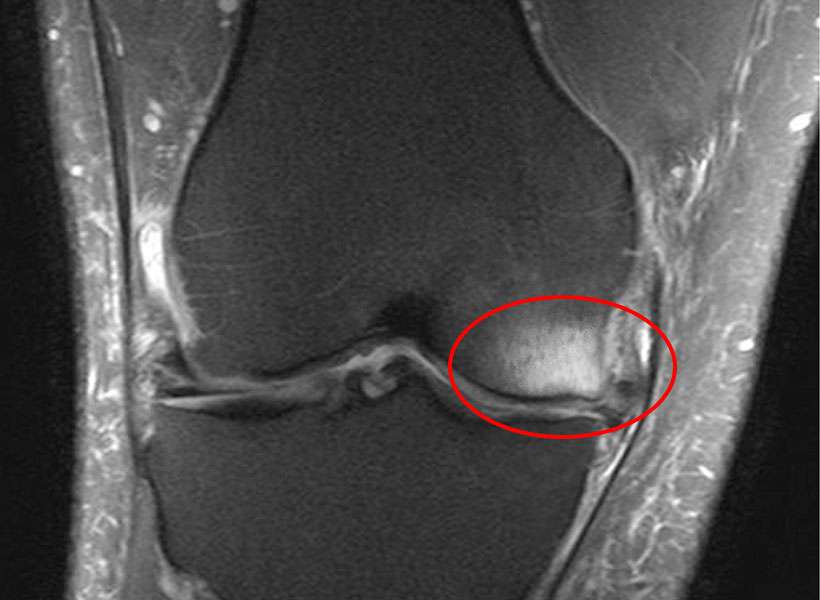

BML are typically not visible on X-rays. They are diagnosed using certain types of MRI, where they appear as a hazy white area against the background of darker bone. Pathologists have shown that these BML represent a healing response surrounding trauma, such as microtrabecular fractures of the subchondral bone.